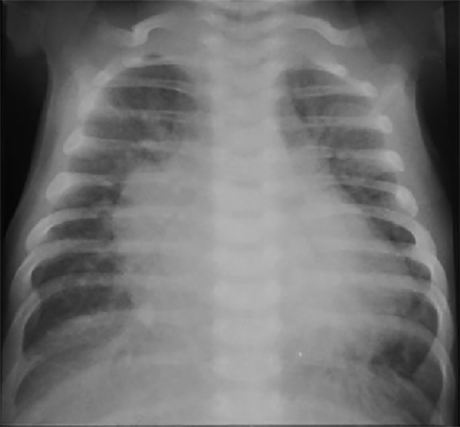

Infant with Large VSD

This is the PA chest X ray of a 3-month-old infant with a large ventricular septal defect. It demonstrates increased pulmonary vascular markings and generalized cardiomegaly. Characteristic features include

prominent vascular densities extending out from the mid line

reflecting large central pulmonary arteries.

Large cardiac silhouette

reflecting enlargement of both right and left heart chambers. And

prominent upper left heart border

reflecting a dilated pulmonary trunk. Note also

pulmonary hyperinflation,

reflected by both diaphragms seen at the level of the eleventh rib.